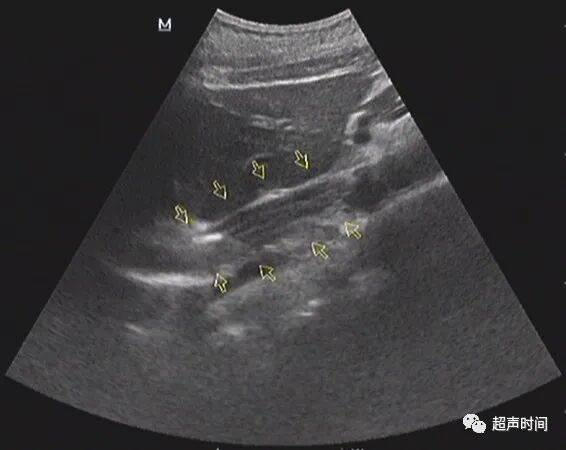

图 3 胃窦纵切:胃窦壁不规则增厚,回声减低,僵直不蠕动

图 4 胃窦横切呈「假肾征」,提示胃壁异常增厚

胃窦壁不规则增厚,回声减低, CDFI :其内可见高阻血流。胃窦壁僵直,探头按压长时间不蠕动。余胃壁蠕动良好。

超声提示:胃窦病变,考虑胃窦癌(建议胃镜活检及增强 CT 检查)